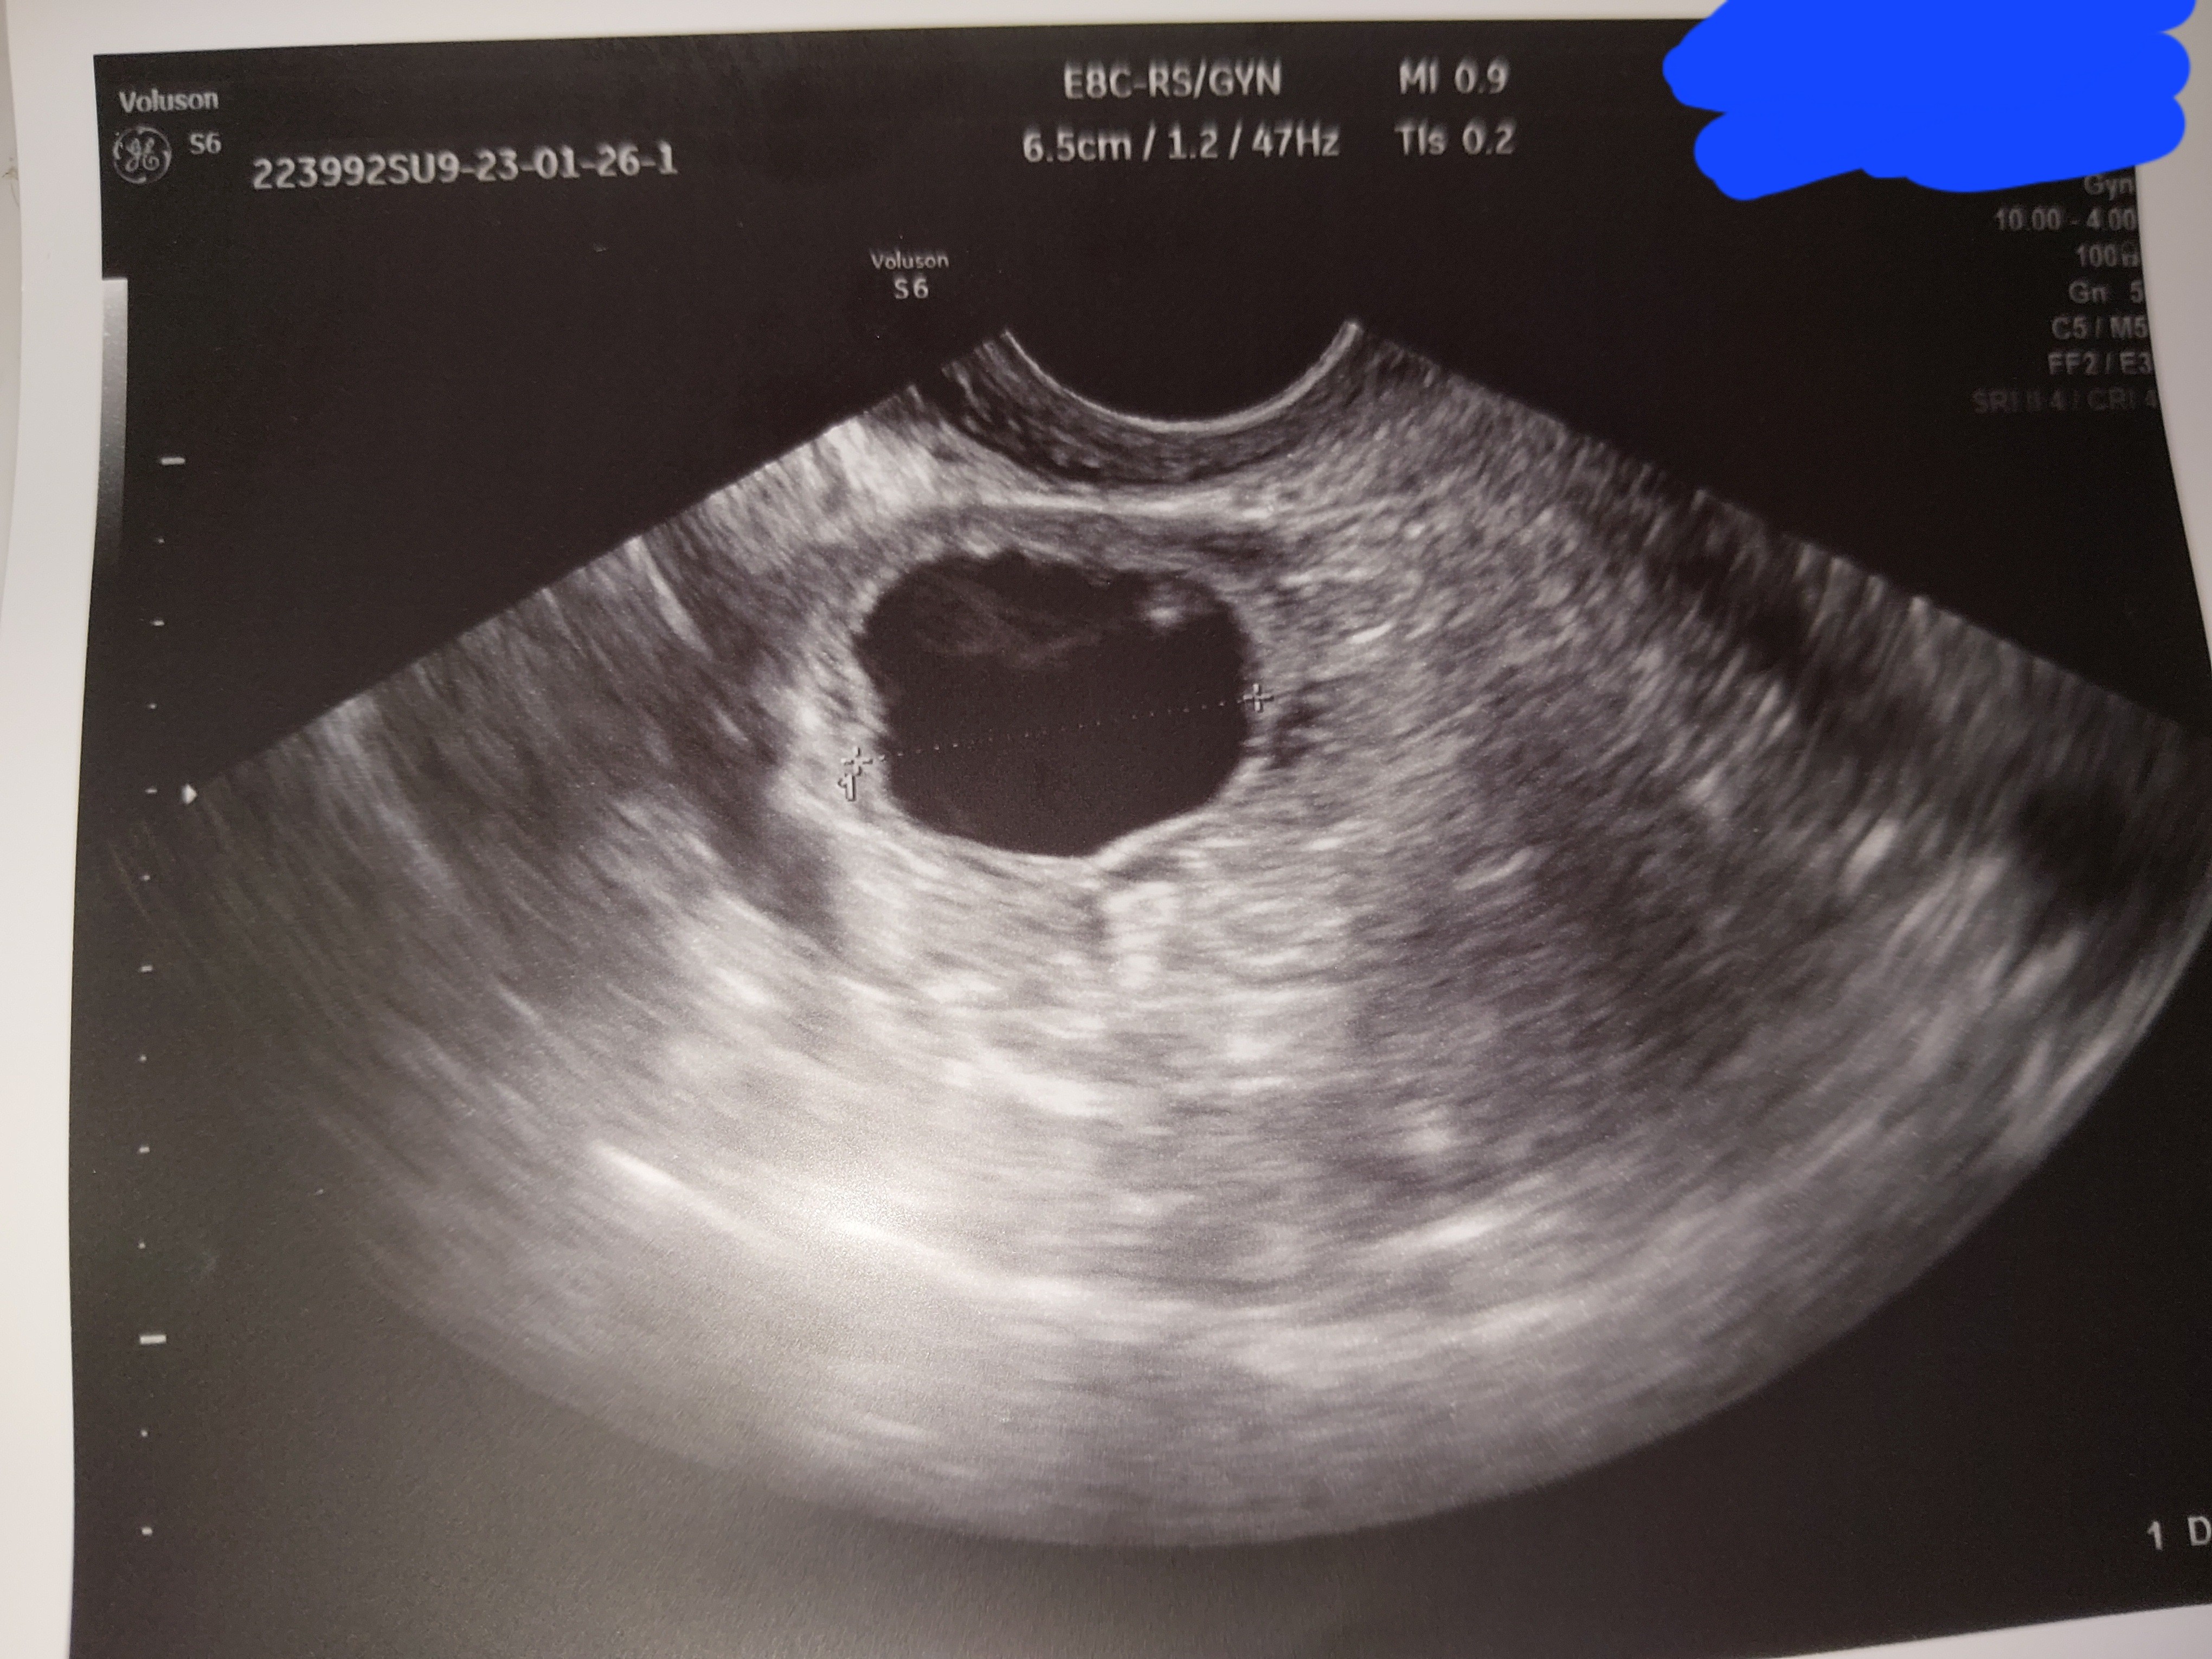

Usg

Czy to ciąża ?

Pecherzyk w prawym jajniku 24 mm( tak wiem może tak wyglądać pecherzyk graffa wraz w wzgórkiem jajonośnym przy owulacji ) Ale czy to na pewno nie jest zarodek ??

Beta 5 tyg po stosunku <0.1

Usg 5.5 tyg po stosunku( i tak musiała się udać , że względu na kontrolę)

Przesyłam zdjęcia i prosiałbym o wytłumaczenie ( chodzi mi głowie o tą kropeczkę w środku pęcherzyka)i może jak ktoś się zna na tych oznaczeniach co one znaczą